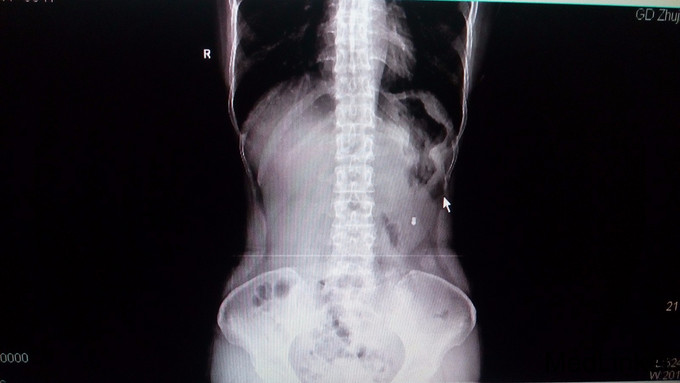

诊断:粘连性肠梗阻 处理:明确无手术禁忌症后,全麻下行剖腹探查术,术中见肠粘连,小肠梗阻,行肠粘连松解术+病变部位肠切除术+肠吻合术。术程顺利,术后予补液、抗感染、营养支持等对症治疗。术后复查立位平片提示腹腔内积气肠管明显减少。